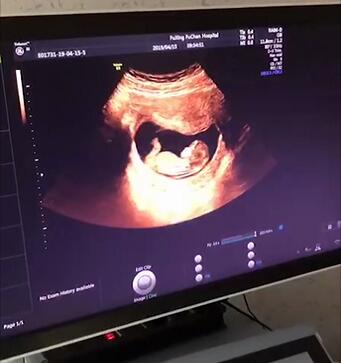

01.超声检查

孕5~8周,通过超声检查,大致能看到胚囊在子宫内的位置,筛查是否有宫外孕的可能。

同时,在孕期5~8周间,还可以看到胚胎数目,以检查是否孕育了多胞胎!

02.NT检查、建档

孕11-13周+6,进行NT(颈后透明层厚度)超声检查,是早孕期产前筛查的重要项目,能筛查出可能性较高的胎儿异常,为孕妈们孕育健康宝宝提供了强有力的保障。